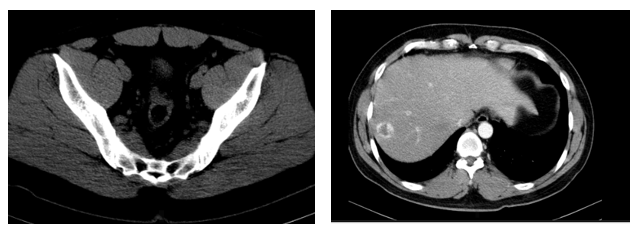

- Chụp cắt lớp vi tính ổ bụng: Nốt đặc xương thân -cánh trái xương cùng kích thước 15×8 mm và xương cánh chậu trái kích thước 13×9 mm. Hình ảnh theo dõi u máu gan phải/ gan nhiễm mỡ

Hình 4: hình ảnh chụp cắt lớp vi tính ổ bụng sau điều trị 10 tháng không có tổn thương nghi ngờ thứ phát